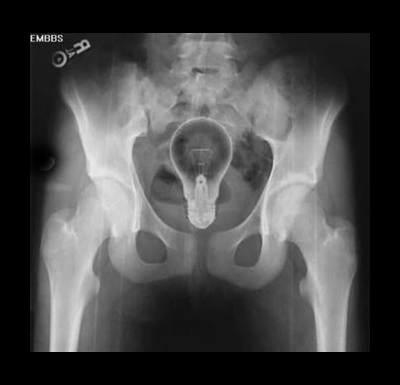

Foto X-Ray Objek Aneh Tertinggal Dalam Organ Intim

mentol...vibrator...dildo...

eeee..tk takut pecah ke mentol tuuu duduk dalam tuu  |

keamatan cahaya yang kuat diperlukan ketika malam hari.....MENTOL |

mentol pun ada......kalau nyala mentol tu lagi best! |